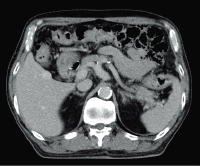

Abdominal CTA (100kV)

Hepatic hemangioma (Dynamic)